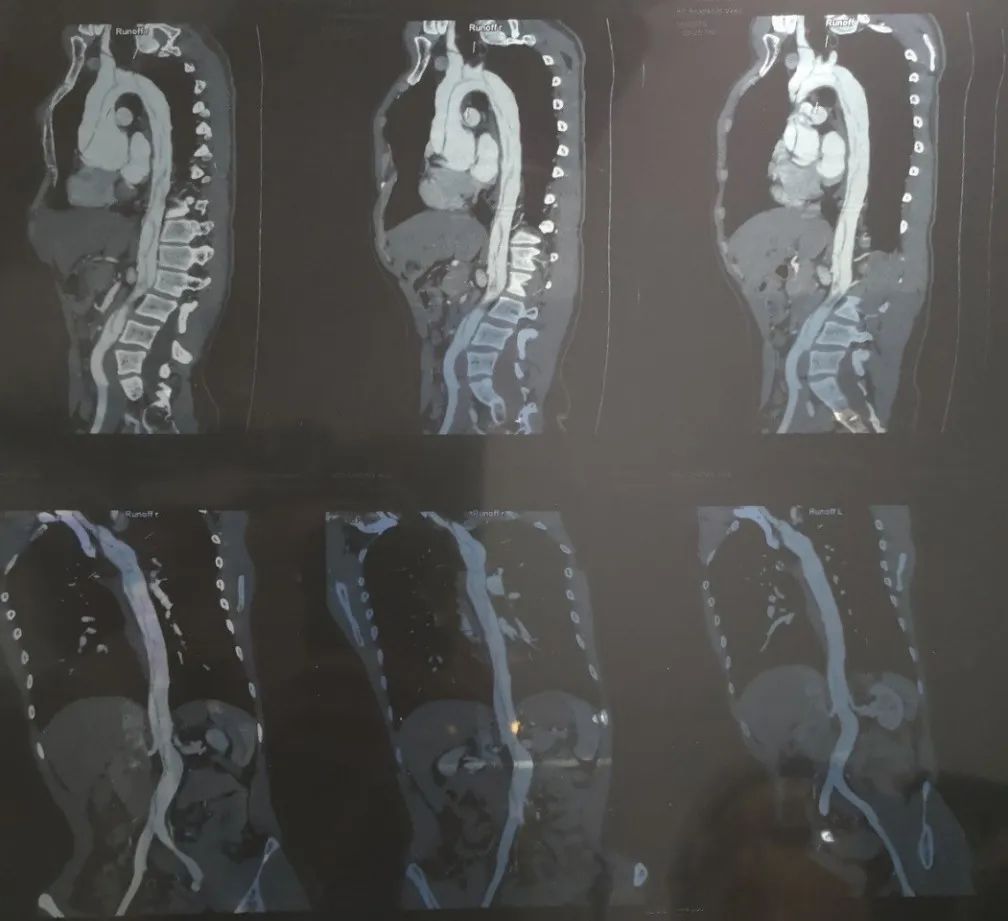

救护车一路风驰电掣,在很短的时间里,就近把我送到了南京军区总医院。接下来急诊医生采取了一系列稳定血压的手段,随后给我做了主动脉造影增强CT,结果出来了病因也确定了,是主动脉夹层,一种我第一次听说的疾病。

当时的CT,可以很清楚地看到夹层的真假两腔以及异常粗大的主动脉根部。丨作者供图

现在回想起当时的凶险,我庆幸自己就医及时,没有造成不可挽回的悲剧。但我日后的生活,还是有很多不确定性。由于当时情况危急,主治医师综合考虑之后,为我替换了主动脉瓣膜和升主动脉,但由于夹层发生时血液的急速扩张,夹层一直扩张到腹主动脉,也就是说我的主动脉弓、胸主动脉以及腹主动脉的绝大部分血管还处于一种真假腔共存的夹层状态。如果我能提早意识到身体存在的问题,在夹层发生前及早治疗,那么现在可能会有更高的生活质量。所以,时间就是生命。

6年时间过去了,我现在自我感觉还好,因为患病的缘故,生活习惯倒是越发健康,也算是因祸得福。我需要每年查一次胸腹主动脉造影增强CT,以监控主动脉扩张程度,一旦达到临界值,可能就要进行后续手术。除此之外,由于更换了机械瓣膜,我需要每天按时服用抗凝的华法林,并且定时监测凝血功能。